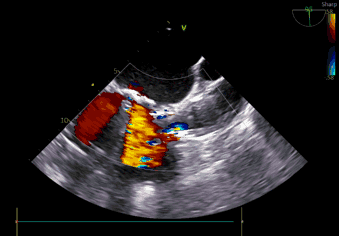

左冠灌注

术中导丝跨瓣后20mm球囊预扩,超声判断冠脉风险尚可,植入L23 VenusA Plus可回收瓣膜位置良好,用23mm球囊后扩支架下缘,微少量瓣周漏。